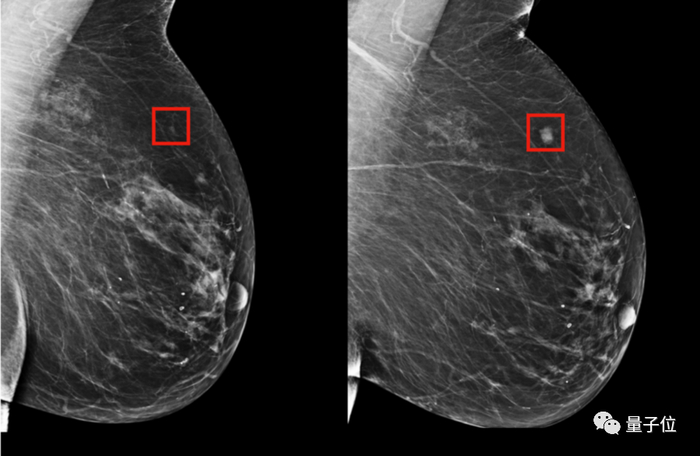

第二个是仅基于X光片图像的深度学习模型;用PyTorch构建了一个深度卷积神经网络ResNet。给定一个乳房的1664 X 2048像素图片,模型会预测是否会在5年内发展成乳腺癌。